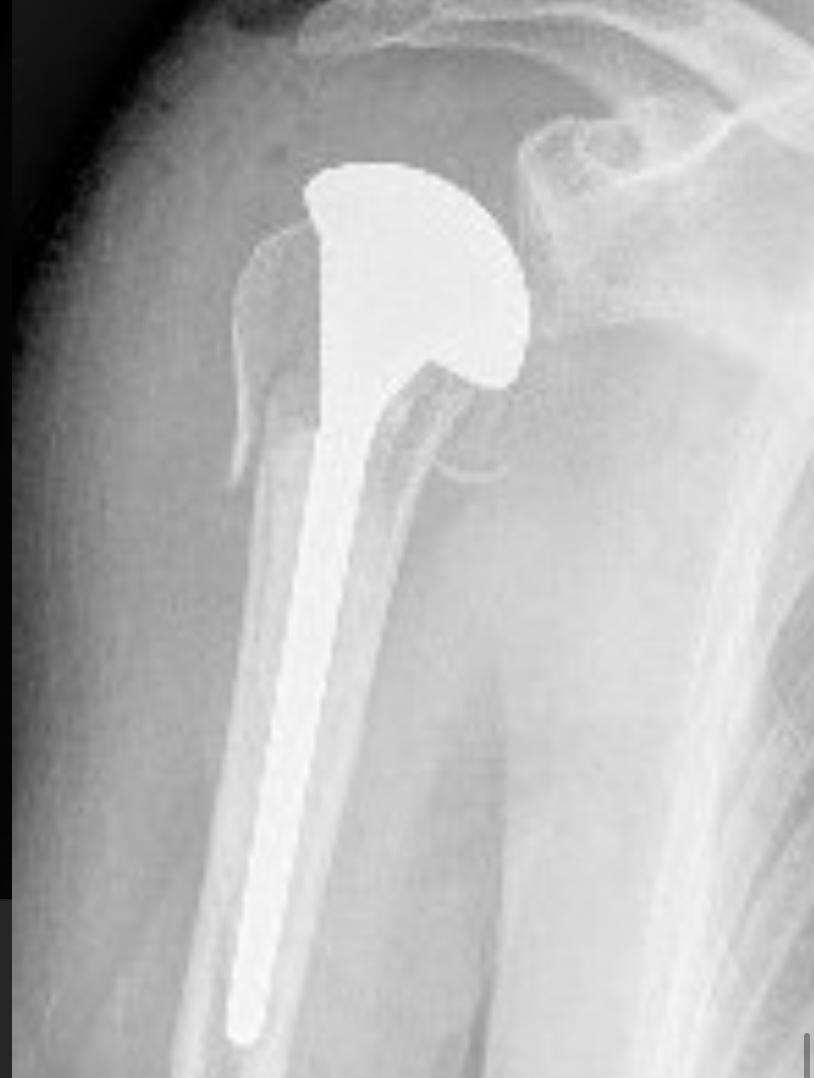

As fraturas do úmero proximal acontecem basicamente em 2 perfis de paciente: em jovens após acidente de alta energia, principalmente queda de moto, e outra, no paciente acima de 50 anos, que simplesmente caem, frequentemente relacionada ao osso com osteoporose. Dor no ombro, impossibilidade de mexer e hematoma. Este último pode se espalhar pelo peito e braço Após a avaliação médica, no serviço de emergência, exame de raio-X será solicitado. Algumas vezes a tomografia computadorizada esclarece detalhes quando a fratura é complexa. Ressonância magnética é solicitada nos casos em que a suspeita de fratura é grande, porém o exame radiológico é normal. São os casos de fraturas ocultas. O tratamento para a maior parte dessas fraturas é com tipóia. Repouso do membro acometido por aproximadamente 45 dias é suficiente para a consolidação do osso. A cirurgia é realizada para aqueles pacientes que apresentam grande desalinhamento dos fragmentos da fratura, fraturas dentro da articulação e fraturas com luxações. O principal meio de fixação é com placa e parafusos. Algumas vezes, dependendo do tipo de fratura e idade do paciente, é necessário substituir a região fraturada por uma prótese.

ARTROSE DO OMBRO

A artrose do ombro constitui o ‘’desgaste’’ da cartilagem da articulação. O principal sintoma é a dor e a rigidez, com a perda progressiva do arco de movimento do ombro. O diagnóstico é realizado através de radiografias que evidenciam o desgaste da cabeça do úmero e do espaço intra-articular e com exame fisico. A artrose não tem cura e os tratamentos aplicados são para evitar a progressão e aliviar os sintomas. O tratamento pode se dividido em não cirúrgico com a utilização de anti-inflamatórios, analgésicos e fisioterapias. E o tratamento cirúrgico no qual é utilizado a prótese, uma peça de metal que substitui a articulação gasta.